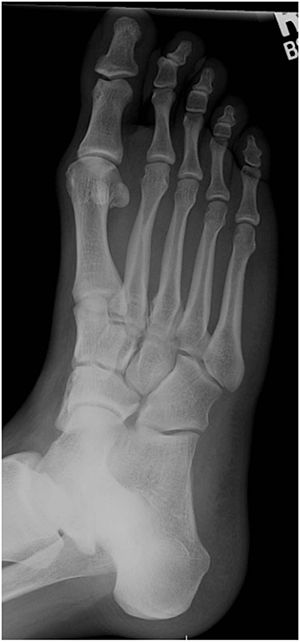

Leg bones (ossa pedis)[edit | edit source]

Tarsal bones ( ossa tarsi ) [edit | edit source]

There are 7 metatarsal bones forming the tarsus pedis :

- Ankle bone (talus) - articulated with the bones of the lower leg, its parts are trochlea, collum, caput (articular surface for articulation with os naviculare), processus posterior - extends backwards, there is a groove called sulcus tendinis musculi flexoris hallucis longi;

- The heel bone (calcaneus) - the largest, anteroposteriorly elongated bone of the instep, has 3 articular surfaces on the dorsal side of the bone - facies articularis talaris anterior, media, posterior , sustentaculum tali - a protrusion of the heel bone supporting the talus, the other parts are the tuber calcanei (a conspicuous structure, clamps with the tendon of the triceps muscle − Achilles tendon ) and facies articularis cuboidea ;

- Navicular bone (os naviculare) - proximally the articular surface for the caput tali, distally 3 triangular surfaces for the ossa cuneiformia, there is a noticeable roughness - tuberositas navicularis, which is palpable in the living;

- Cuboid bone (os cuboideum) − irregular shape, proximally it has a wavy curved articular surface for connection with the calcaneus, distally articular surfaces for metatarsal axis IV and V and medially articular surface for connection with the external sphenoid bone;

- Cuneiform bones (ossa cuneiformia) - there are three: os cuneiforme mediale (the largest), intermedium and lateral.

In the assembly of the metatarsal bones, we find 2 proximodistal stripes :

- In the assembly of the bones of the metatarsals we find

- internal − talus − os naviculare − 3 ossa cuneiformia − 3 ossa metatarsalia

- outer − calcaneus − os cuboideum − 2 ossa metatarsalia

Metatarsal bones ( ossa metatarsi ) [edit | edit source]

These are 5 metatarsal bones ( os metatarsale ), designated by the Roman IV. Each has 3 parts − basis, corpus, caput . Together they form the metatarsus of the foot (instep). They are similar in structure, development and ossification to the metacarpus of the hand.

Bones of the toes ( ossa digitorum pedis ) [edit | edit source]

The skeleton of the fingers is formed by the phalanges digitorum pedis . Each finger has 3 joints − phalanx proximalis, media et distalis , the exception is the thumb, which has two joints (it does not have a phalanx media). Each article can again be divided into 3 parts - basis, corpus, caput .